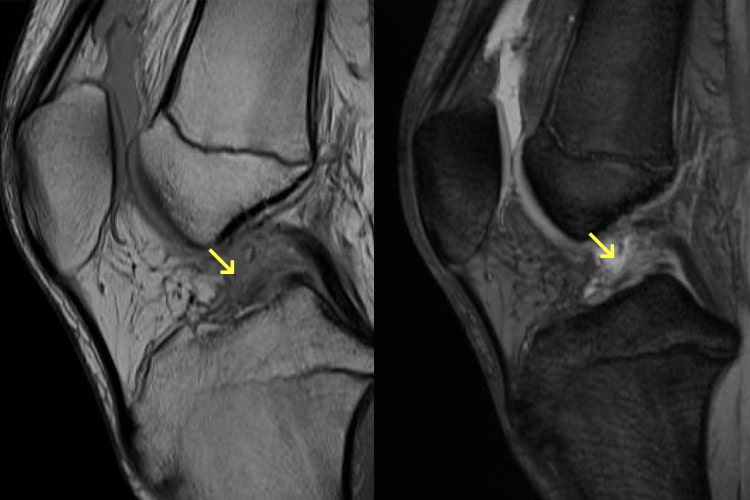

頚椎症性脊髄症

ボタンのかけ外し、お箸の使用、書字が不器用になったり、歩行で脚がもつれるような感じや手足のしびれも出てきます。比較的若い方であれば、かけ足やケンケンをしにくくなるなどの軽度の症状を自覚できますが、高齢者では気づくのが遅れる場合があります。転倒などの軽微な外傷で四肢麻痺(脊髄損傷)になる危険性がありますので、転倒しないように注意します。一般的に日常生活に支障があるような手指巧緻運動障害や痙性歩行障害、神経因性膀胱などが見られるようになれば手術的治療が選択されます。